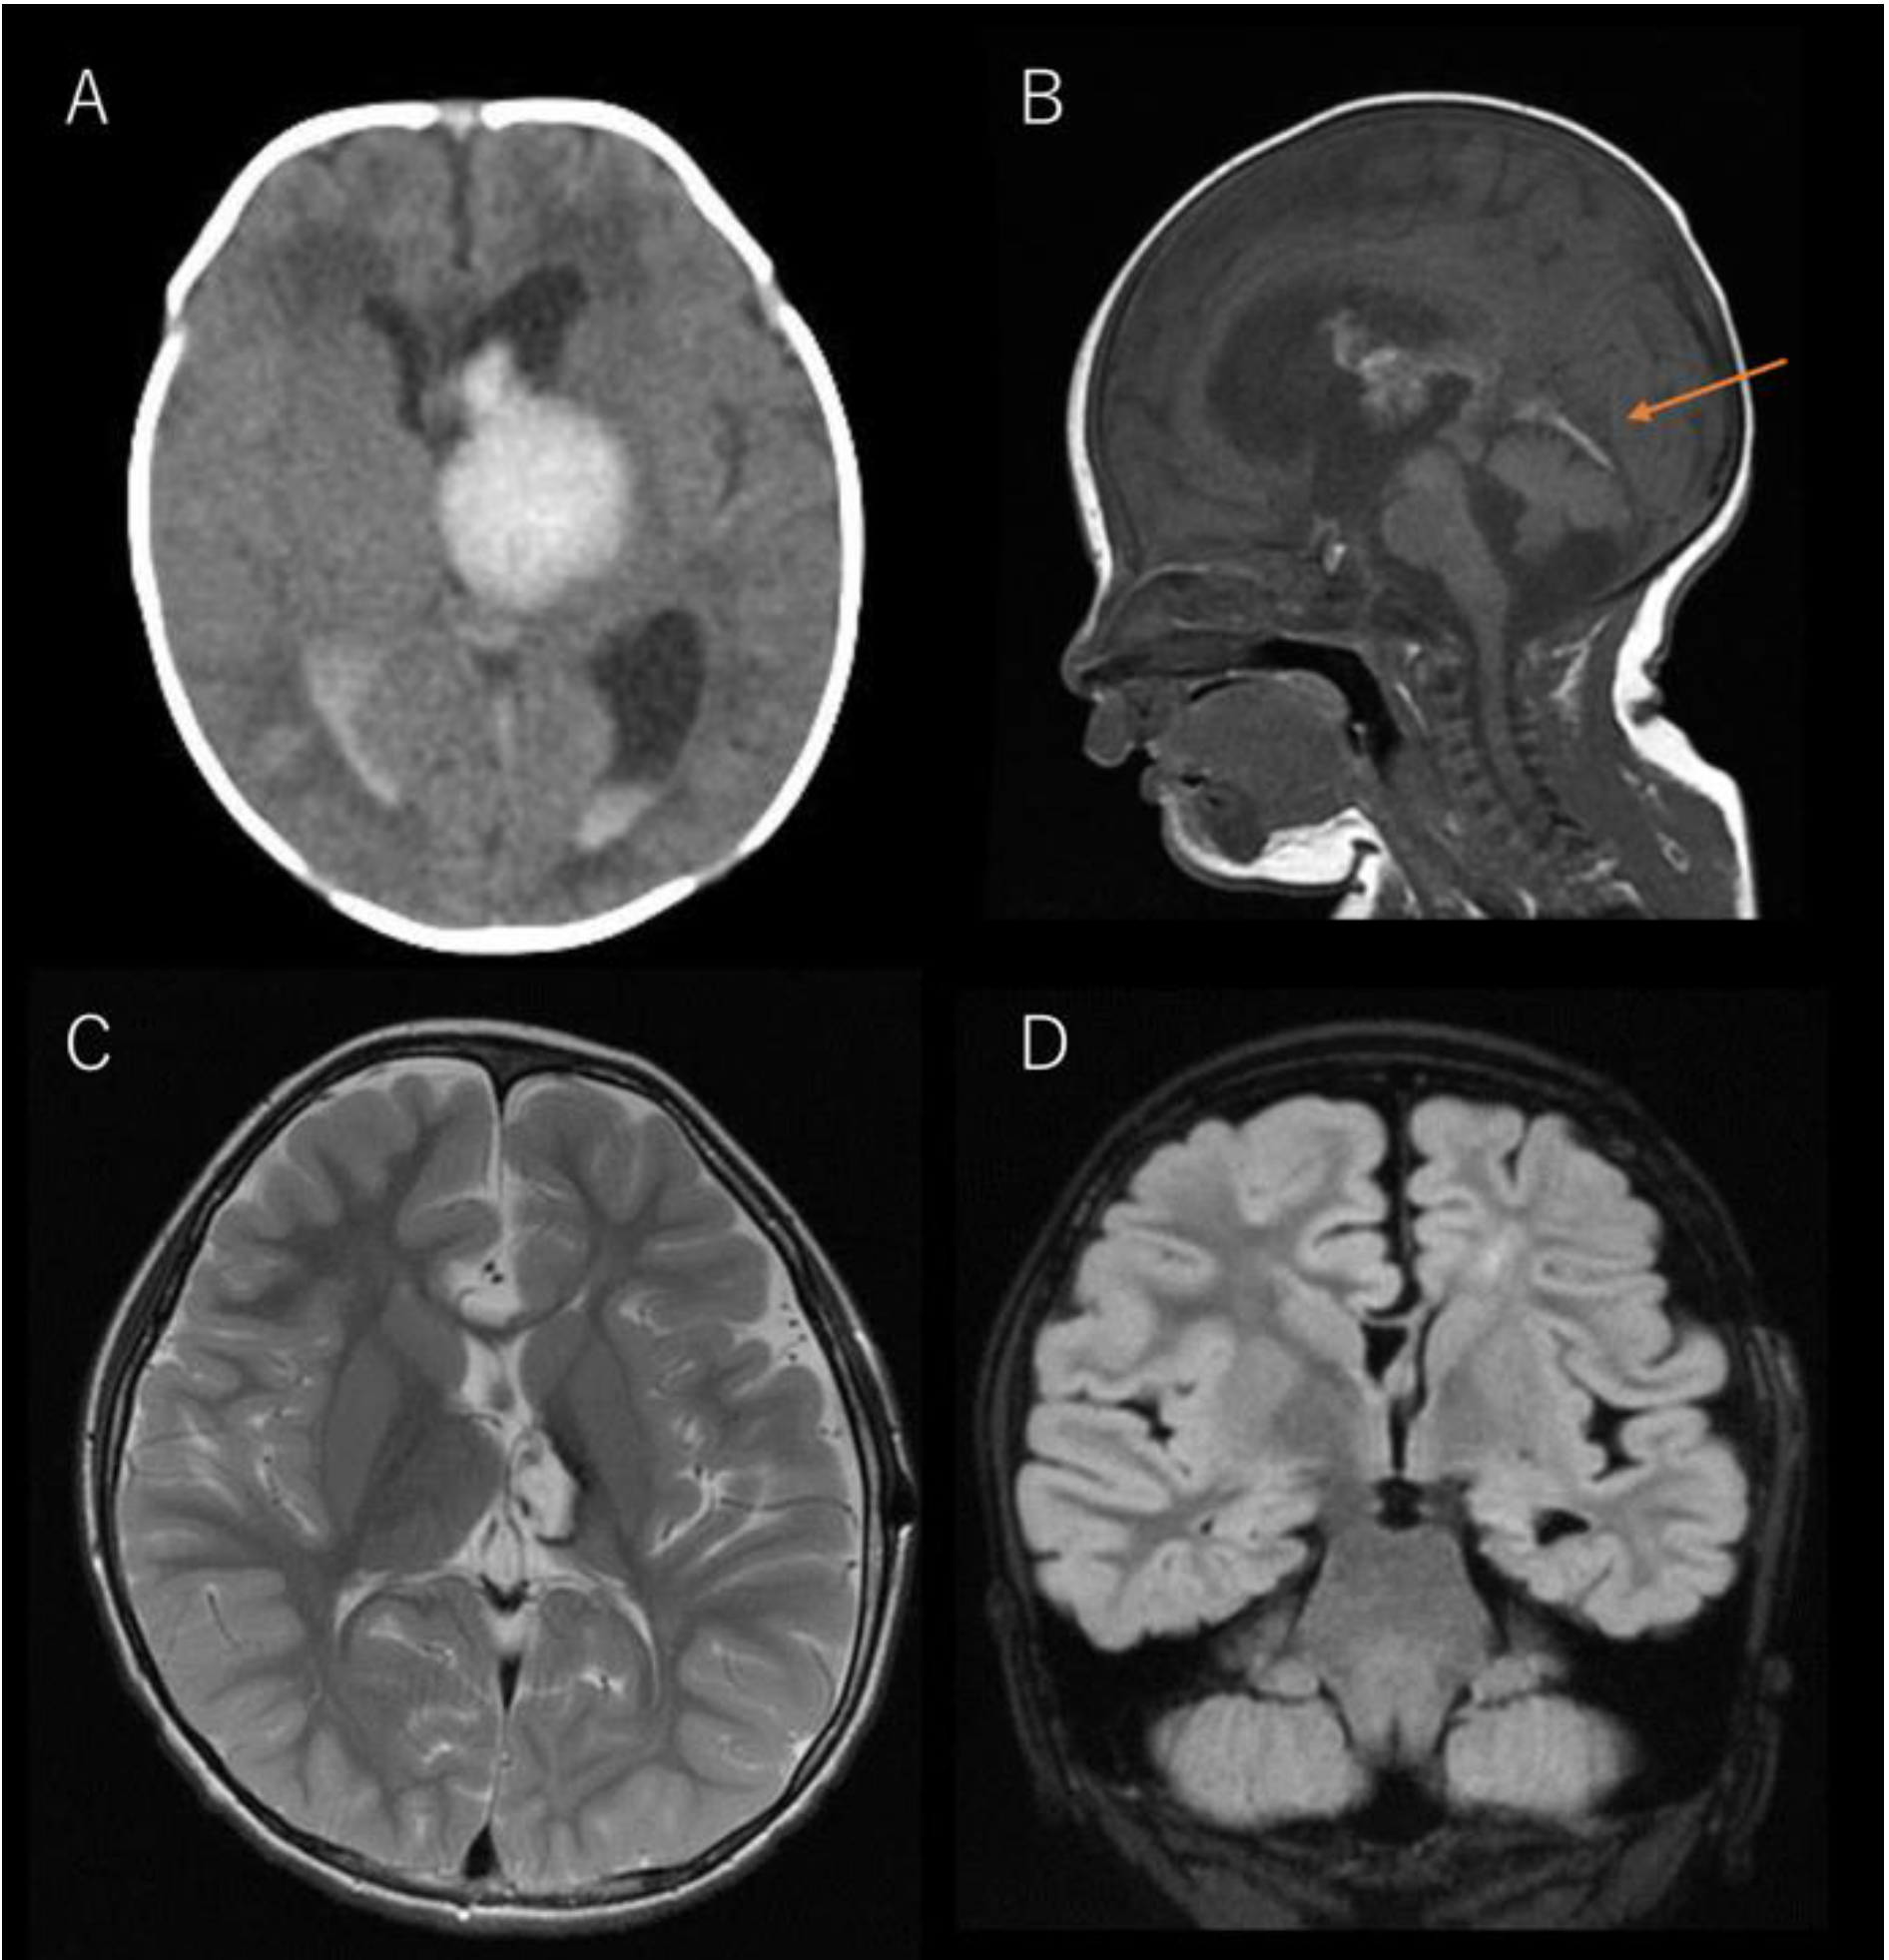

The CT scan of thalamic hemorrhage before and after THD. (A Thalamic Hemorrhage Treatment Treatment principle of thalamic hemorrhage is evacuation of the hematoma, removal of the occupying effect, alleviation of. For clinicotopographic analysis, we determined four types of thalamic hemorrhage, as described elsewhere: Treating a thalamic stroke is focused on prompt. The goals of initial treatment include preventing hemorrhage expansion, monitoring for and managing elevated intracranial pressure,. Thalamic strokes cause specific symptoms, such. Thalamic Hemorrhage Treatment.